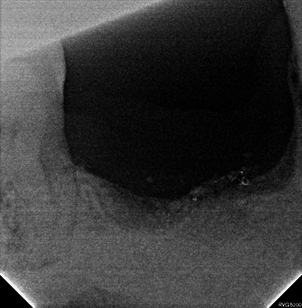

Intraoral photograph and panoramic radiograph at 4 months post-GBR.

Maxy was performed at #45 due to dense areas within the grafted bone.

An ALX-IT 5.5 × 6 mm, Cuff 3 mm was placed at #45, achieving 40N/cm of insertion torque.

Post-operative panoramic radiograph

Clinical photograph and PA radiograph at 3-month follow-up showing well-maintained prosthetic stability.